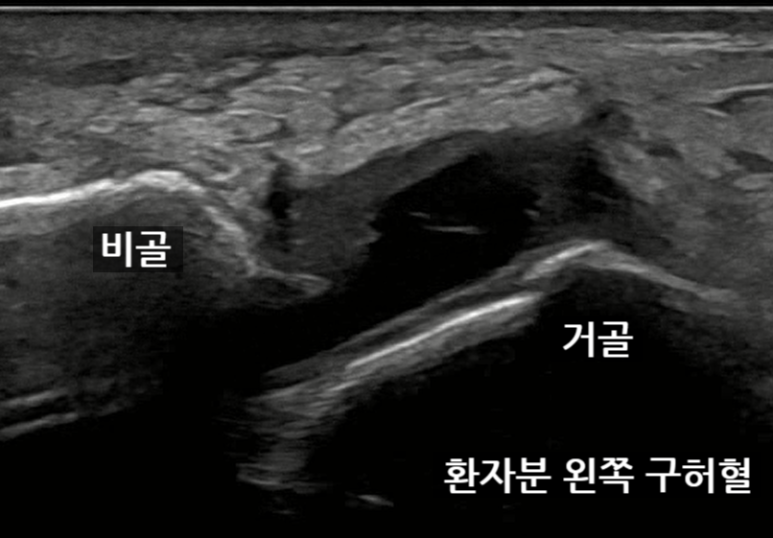

하지만 우리 환자분

왼쪽 발목 구허혈은

전거비 인대가 완전파열되어

인대가 보이지 않고

관절도 까맣게 부어있습니다.

인대가 완전 파열되어서

두 뼈를 고정해주지 못하면요.

거골과 비골 사이 간격이

4mm 이상 벌어집니다.

안정시에

두 뼈 거리는

1.92cm 였고요.

내번 스트레칭할 때

두 뼈 거리는 2.33cm로

4.1mm 벌어집니다.

구허혈에서 확인한

경혈 초음파 소견상

전거비인대가제 기능을 못하는 상태네요.